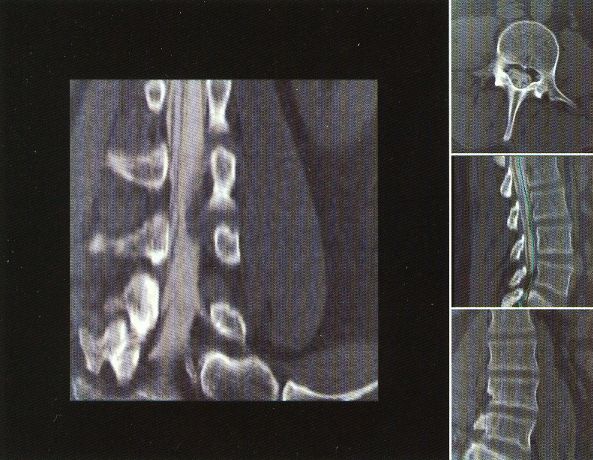

The first workstation to be seriously marketed was Voxelscope II (VS2) which had greatly enhanced volume memory and higher display resolution. Unfortunately, that came at a cost and it, and all its successors never even came close to achieving the true video-rate real-time performance of the VPP, which would have required the massively parallel technology in the Patent. But even very early on, VS2 had somewhat real software with a Graphical User Interface (GUI) and enough functions to be credible, at least for demos including instantaneous Multi-Planar Reformatting (MPR) which could display a slice though the object at any depth aligned with one of the principal axes (axial, saggital, or coronal) or at an arbitrary angle, as well as real-time (fraction of a second, but not video rate) 3-D shaded surface with density selection and slicing. A Motorola 68000-based VME bus single board computer replaced the PDP-11 or VAX (sorry DEC) and implemented the high level control and Graphical User Interface (GUI), ran the file system, and interfaced to the outside world.

These photos of the Voxelscope II screen are typical of the types of rendering provided by the system.

Voxelscope II Screen Shots. Combination of 3-D Shaded Surface, Multiplanar Reformatting, and Segmentation

Of course, once there was a real Marketing department, the real Software types (led by Eddie Wyatt) were always slowing things down anyhow in the interest of generality - or to concentrate on features users might actually care about! What a conecpt? ;-) One example was Multi-Planar Reformatting or MPR where a single cut along one of the principal planes - axial (XY), saggital (YZ), coronal (XZ) - or at an arbitrary angle or even curved cut through the object is displayed. MPR could have run at full video rates on any of the machines, but no matter how hard I tried to convince Software to improve the performance, it never chugged along at more than a couple frames per second. :( :) And large portion of the VS2 hardware capabilities were never exploited due to feature priority as determined by Marketing.